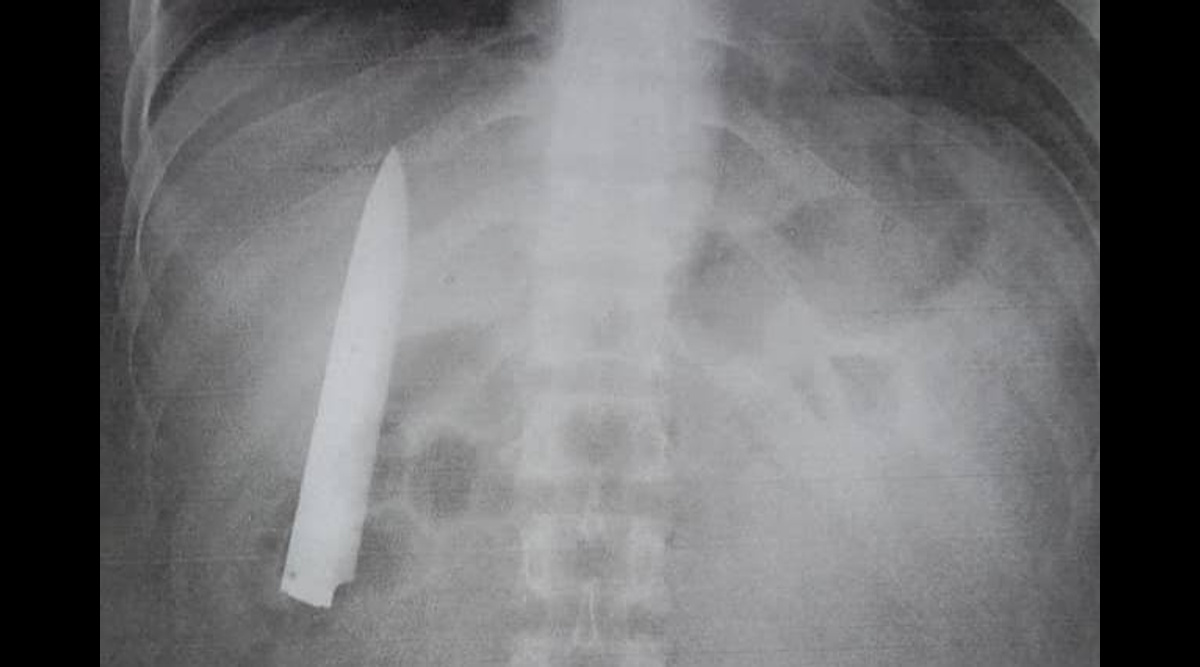

Странная история произошла с 26-летним парнем из филиппинского города Кидапаван. Кент Рян Томао нашёл хорошую работу на шахте и проходил для неё медосмотр, когда рентген показал кое-что необычное. Оказывается, в грудной клетке парня засел нож длиной 10 см, который находился в опасной близости от лёгкого, пишет .

Кент припомнил, что в январе прошлого года он возвращался с работы домой, когда на него напал грабитель и ранил ножом. В больнице парню дали обезболивающее и зашили рану, не делая дополнительных снимков. С тех пор Кента мучила боль в груди, особенно в плохую погоду, но она никогда не была настолько сильной, чтобы обращаться к врачам. А теперь парень узнал, что во всём был виноват нож, который врачи забыли из него достать.